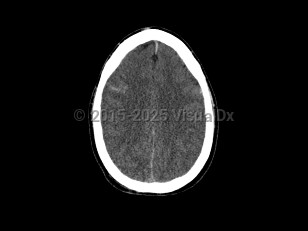

Imaging Studies image of Cerebral edema - imageId=7877814. Click to open in gallery.  caption: '<span>Axial CT image demonstrates  diffuse loss of the gray-white matter interface and sulcal prominence.  Findings were consistent with post-traumatic diffuse cerebral edema.</span>'

Axial CT image demonstrates diffuse loss of the gray-white matter interface and sulcal prominence. Findings were consistent with post-traumatic diffuse cerebral edema.